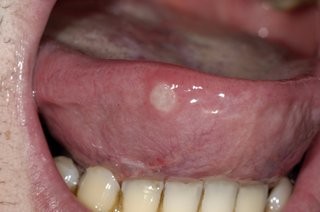

Are you prone to getting mouth ulcers? There are a number of different contributing factors and presentations of mouth ulcers; and thankfully most are harmless and heal on their own. However, there are some that can appear very similar but are in fact far more serious. If your mouth ulcer isn’t healing, we recommend you visit us immediately to assess the possibility of mouth cancer. Any mouth ulcer that has been present for more than three weeks must be treated as serious until proven otherwise.

A mouth ulcer, otherwise known as a canker sore or an aphthous ulcer, occurs when there is a break in the skin of the mouth (mucosal lining), exposing the underlying connective tissue. It may have a 'crater-like' appearance and is often red and painful, similar to a blister in the mouth.

Unlike the relatively benign examples mentioned above, oral cancers may initially show up as a mouth ulcer. Oral cancer can present itself in many ways: some people first become aware of an ulcer that won't heal: these lesions are usually a painless mouth ulcer, but it doesn't come and go the way other mouth ulcers do. Any mouth ulcer that has been present for more than three weeks must be treated as serious until proven otherwise. Similarly, if you have developed a red , white or mixed red and white patch, you must urgently seek a professional opinion.